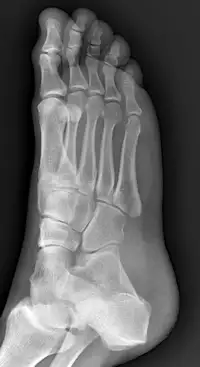

Arthritis

Arthritis is inflammation of one or more of your joints. It can cause pain and stiffness in any joint in the body and is common in the small joints of the foot and ankle.

There are more than 100 forms of arthritis, many of which affect the foot and ankle. All types can make it difficult to walk and perform activities you enjoy.

Although there is no cure for arthritis, there are many treatment options available to slow the progress of the disease and relieve symptoms. With proper treatment, many people with arthritis are able to manage their pain, remain active, and lead fulfilling lives.

Bunions

A bunion is a bony bump that forms on the joint at the base of your big toe. It occurs when some of the bones in the front part of your foot move out of place. This causes the tip of your big toe to get pulled toward the smaller toes and forces the joint at the base of your big toe to stick out. The skin over the bunion might be red and sore.

Wearing tight, narrow shoes might cause bunions or make them worse. Bunions can also develop as a result of the shape of your foot, a foot deformity or a medical condition, such as arthritis.

Smaller bunions (bunionettes) can develop on the joint of your little toe.